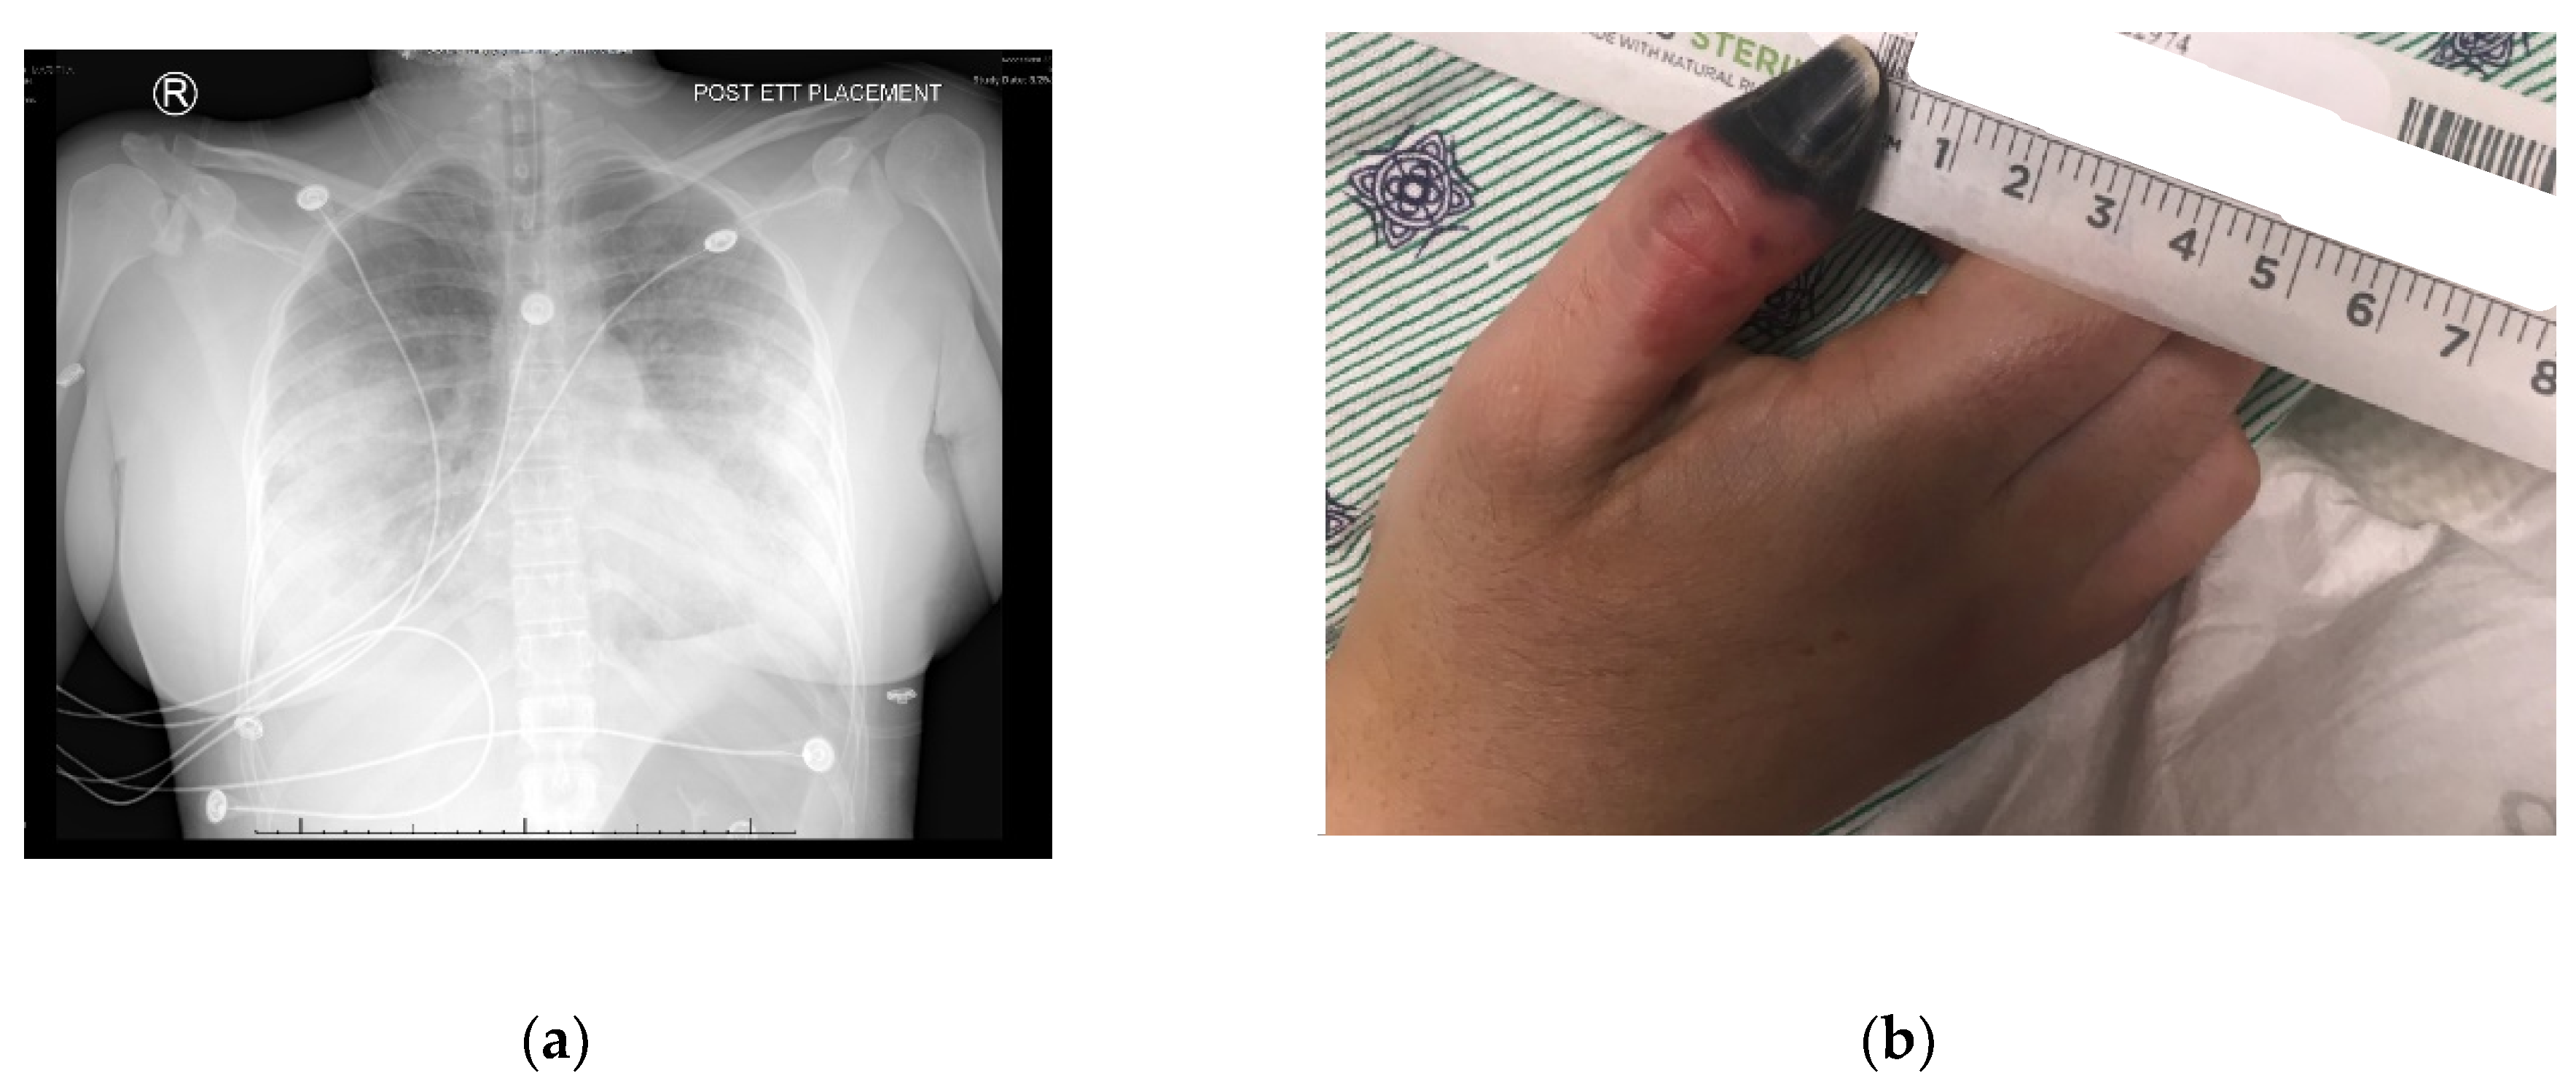

A thirty-one-year-old female (oral informed consent was obtained), with a past medical history of asthma and intermittent cocaine use, developed cough, dyspnea, hemoptysis, fever, and pleuritic chest pain several hours after receiving Bio-Alcamid gluteal injections. Despite a course of Levaquin, she required admission to her local community hospital. Initial workup at the hospital included a lower extremity doppler ultrasound, which was negative for deep vein thrombosis, and a CT without contrast that showed multiple bilateral areas of patchy infiltrates predominantly in the periphery. Occurring on day two of admission, a CT with contrast showed progressive worsening of the infiltrates, with development in the bilateral apices, and the superior and posterior left upper lobe (Figure 1a). Pulmonary artery enlargement, engorgement with redistribution of blood flow, and right-sided pleural effusion also was reported. A right-sided thoracentesis was performed.

The patient remained admitted and required intubation on day three. She was treated with high-dose steroids and antibiotics were broadened to linezolid, meropenem and levofloxacin. A work-up revealed a negative legionella urine antigen test, a negative test for tuberculosis, a negative hepatitis panel and a negative HIV screen. The patient was transferred on day five to a larger Level 1 trauma center with more resources for evaluation of Extracorporeal membrane oxygenation (ECMO). Physicians decided ECMO was not required., The patient, at the time of transfer, responded to Furosemide diuresis, bed proning, and nitric oxide with good response.

Upon arrival to the new facility, the patient was admitted to the Intensive Care Unit (ICU) and started on a Bumex drip and had a 2D-echocardiogram performed. The echocardiogram demonstrated a positive bubble study in the left atrium, suggesting a patent foramen ovale (PFO), severe pulmonary hypertension with a right ventricular mild dilation and reduced function. During the first three days of admission to the new hospital, the patient developed thrombosis of her right radial artery requiring a radial thrombectomy; she required a transfusion of one unit of packed red blood cells and one unit of platelets, plasmapheresis due to a possible TTP, and a Nicardipine (Cardene) drip. Dry gangrene in the distal right thumb developed due to a right radial artery thrombus (Figure 1b). The patient also demonstrated decreased responsiveness while on sedation vacation. A CT of the brain taken during this time reported multifocal acute infarcts involving the bilateral cerebral hemispheres and the left cerebellar hemisphere, given involvement of multiple vascular territories (Figure 2). A CT arteriogram of the brain and neck with IV contrast demonstrated an incomplete occlusive filling defect of the proximal internal jugular vein, raising concern for a partial thrombosis.

Figure 1. (a) Diffuse bilateral effusion- A/P view; (b) Right thumb dry gangrene.